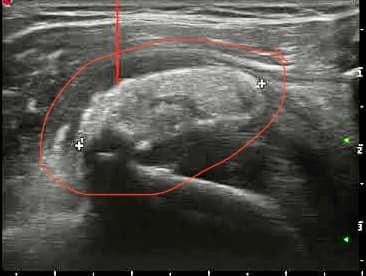

La Dottoressa Morgano Maria Chiara si è laureata in Medicina e Chirurgia presso l’università degli studi di Palermo con 110/110 e Lode. Ha conseguito la specializzazione in Radiologia col massimo dei voti e Lode presso l’università degli studi dell'Insubria. Durante il percorso di specializzazione presso l'Ospedale di Varese "Ospedale di Circolo e Fondazione Macchi", ha acquisito buone competenze diagnostiche come radiologo generale sull'utilizzo di varie metodiche di imaging (RX, ecografia, Tomografia Computerizzata, RM), ma ha dedicato gran parte della sua formazione alla Radiologia Muscolo-scheletrica Diagnostica ed Interventistica, maturando esperienze e competenze nel trattamento ecoguidato di patologie muscolo-tendinee. Ha completato il suo percorso di specializzazione presso "Columbus Clinic Center" a Milano, dove ha avuto la possibilità di seguire un vasto numero di Risonanze su atleti e sportivi come ad esempio giocatori di A.C. Milan, acquisendo competenze specialistiche nell’ambito delle patologie sportive. Ha lavorato come libera professionista presso Vari studi privati nella città di Siena ove praticava l'ossigeno-ozonoterapia sulla colonna per poi lavorare come dirigente medico presso l'Azienda Ospedaliera di Busto Arsizio. Ha lavorato presso l'Ospedale di Carate Brianza, dove ha avviato l'ambulatorio di ecografie muscolo-tendinee ed infiltrazioni eco-guidate. Da gennaio 2026 lavora presso l’ospedale IRCCS Multimedica di Sesto S. Giovanni dove esegue ecografie ed infiltrazioni ecoguidate. Svolge inoltre attività libero-professionale in ambito di Medicina Estetica, integrando alla visita clinica una valutazione ecografica accurata del volto. Questo le permette di utilizzare le competenze ecografiche maturate nella radiologia anche nei trattamenti estetici, al fine di ridurre il rischio di complicanze, indirizzare con precisione l’area da trattare e gestire in modo più efficace eventuali complicanze.

Foto e video